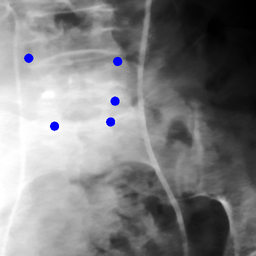

The dataset we use in the experiments is a cone-beam CT (CBCT) dataset captured for radiation therapy. The dataset contains 340 raw CBCT scans with each has 780 X-ray images. Each X-ray image comes with a geometry file that provides the registration ground truth as well as the information to reconstruct the CBCT volume. Each CBCT volume is reconstructed from the 780 X-ray images, and in total, we have 340 CBCT volumes (one for each CBCT scan). We use 300 scans for training and validation, and 40 scans for testing. The size of the CBCT volumes is 448×448×768448448768448\times 448\times 768 with 0.5 mm voxel spacing, and the size of the X-ray images is 512×512512512512\times 512 with 0.388 mm pixel spacing. During the experiments, the CBCT volumes are treated as the 3D pre-intervention data, and the corresponding X-ray images are treated as the 2D intra-intervention data. Sample X-ray images from our dataset are shown in Figure. Note that unlike many existing approaches [15, 17, 25] that evaluate their methods on small datasets (typically about 10 scans) which are captured under relatively ideal scenarios, we use a significantly larger dataset with complex clinical settings, e.g., diverse field-of-views, surgical instruments/implants, various image contrast and quality, etc.

We consider two common views during the experiment: the anterior-posterior view and the lateral view. Hence, only X-rays that are close to (±5°plus-or-minus5°\pm 5\degree) these views are used for training and testing. Note that this selection does not tightly constrain the diversity of the X-rays as the patient may be subject to movements with regard to the operating bed. To train the proposed method, X-ray and DRR pairs are selected and generated with a maximum of 10°10°10\degree rotation offset and 202020 mm translation offset. We first invert all the raw X-ray images and then apply histogram equalization to both the inverted X-ray images and DRRs to facilitate the similarity measurement. For each of the scan, we also annotate their landmarks on the reconstructed CBCT volume for further evaluation.

Refer to caption

Figure 6: Sample raw X-ray images of our dataset.